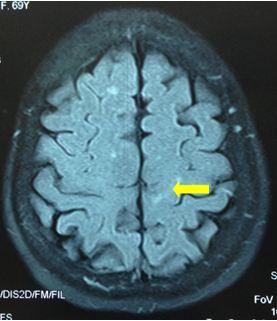

Chụp MRI sọ não (12/12/2011):

Hình 2: Hình ảnh chụp MRI sọ não có khối u não vùng đỉnh trái, 20×19mm, ngấm thuốc quanh u

Chụp MRI sọ não: Sau xạ phẫu 6 tháng bằng dao gamma quay: khối u não tan biến hoàn toàn

Trước điều trị: u não 20×19mm

Sau điều trị 6 tháng: u tan hoàn toàn

Trước điều trị: u 20×19mm

Hình 6: Hình ảnh chụp MRI sọ não sau 6 tháng xạ phẫu bằng dao gamma quay: Khối u não di căn vùng đỉnh trái tan hoàn toàn